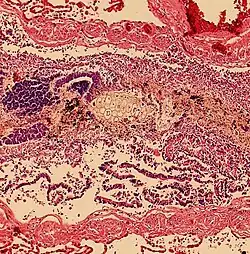

Aspiration pneumonitis

Aspiration pneumonitis (Mendelson's syndrome) is chemical injury of lung tissue secondary to aspiration of regurgitated gastric acid.[15] The syndrome was first described among pregnant patients[16] after the administration of anesthesia, though it can occur in any scenario where gastric contents are aspirated.[17]